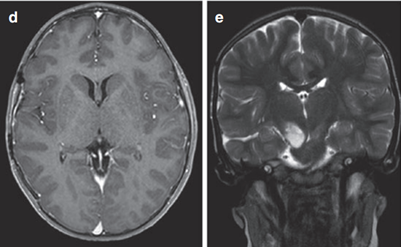

患者是一名6歲男童,癥狀為頭痛、間歇性左上肢震顫。MRI (FLAIR序列)顯示一個(gè)兩側(cè)丘腦腫瘤,右比左大,尾狀核的右頭部也參與其中。腦室輕度增大,膈膜水腫,腫瘤內(nèi)部囊腫。因此,Rutka教授為其先行左額部?jī)?nèi)窺鏡活檢和鼻中隔造瘺術(shù),再行左枕腦室-腹腔分流術(shù)。

丘腦膠質(zhì)瘤

圖8

組織病理診斷為WHO III級(jí)間變性星形細(xì)胞瘤,H3K27M、p53、BRAF V600E突變免疫陰性。MIB-1增殖指數(shù)為40%。至此,Rutka教授為患兒制定了周密的綜合治療方案,患兒開始同時(shí)接受替莫唑胺(TMZ)和放射治療(59.4 Gy),并接受累計(jì)劑量為200 mg/m2的12個(gè)周期的持續(xù)替莫唑胺治療。該男孩在確診后15個(gè)月放射學(xué)表現(xiàn)穩(wěn)定,癥狀也得以緩解,生活質(zhì)量有所提升。